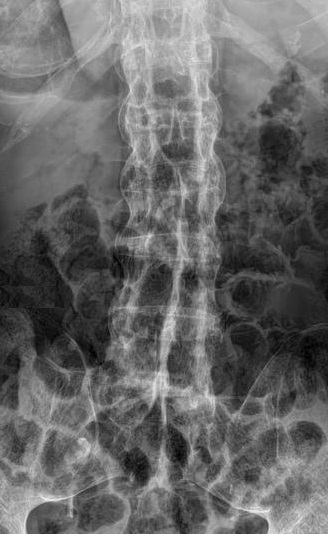

Image radiologique PA

d'une fibrose pulmonaire avec aspect de fibrose de

articulaire sterno-claviculaire gauche d'une

spondilite ankylosant |

Une autre cas de PSA du

thorax en association de lesion du corp

vestebrale.Image radiologique IRM en coupe sagital à

ponderation sur T1 |